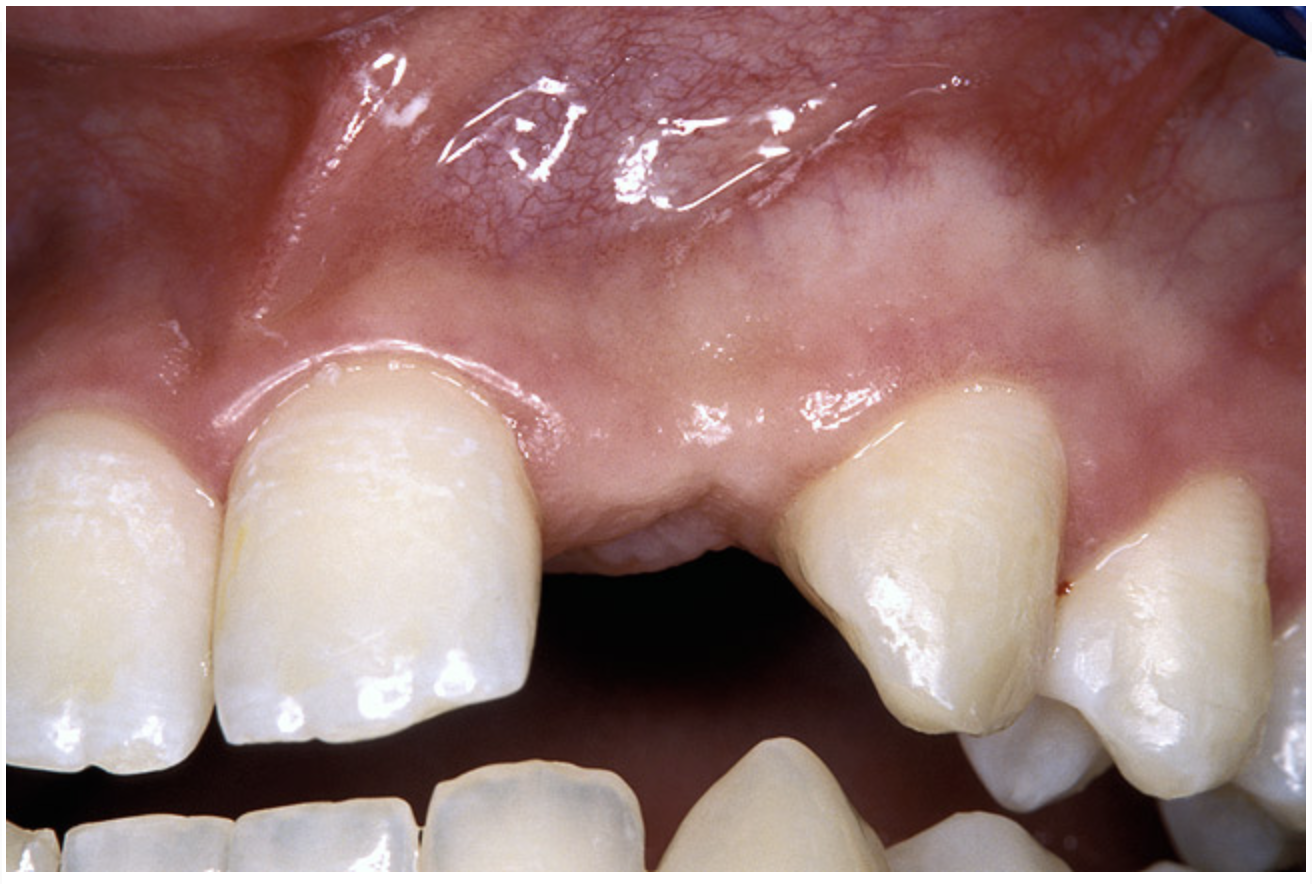

A 17-year-old boy presented with a history of congenitally missing maxillary lateral incisors. The patient had been under the care of an orthodontist for several years to manage his occlusion during his adolescent growth phase. The patient originally presented with his parents after being told that the “braces were ready to be removed, and their son was now ready for implants to replace the missing teeth.” This is not an uncommon circumstance, and unfortunately the orthodontic alignment was performed before the patient was sent to the restoring dentist. Therefore, the orthodontist was not aware of the space requirements for future implant placement. This case highlights the importance of proper communication between all members of the implant team, especially during the orthodontic planning phase. The patient’s medical history was unremarkable, and the patient was found to be healthy and a good potential candidate for dental implants to replace the missing lateral incisors.

Periapical radiographs were taken to help determine the mesial-distal inclinations of the adjacent tooth roots (Figure 1). The radiographs revealed a serious issue, convergent roots for the right canine and right central, which eliminated that area as a potential implant-receptor site. The space between the left central and canine teeth was minimal, although the roots were relatively parallel. Clinical examination (manual palpation of the root eminences superiorly to the vestibule on the right side) confirmed the root convergence (Figure 2A). The flat, wide zone of the keratinized tissue and lack of interdental papilla was evident for the missing right lateral incisor. There was a marked difference in clinical appearance for the left lateral, which could impact the eventual plan of treatment (Figure 2B). Other significant clinical findings included bilateral facial bone concavities, which existed as a result of the congenitally missing tooth roots. As a diagnostic cue to the underlying bone topography, it is important to follow the demarcation between attached and unattached gingival tissue, and note the crestal width of the available keratinized tissue (Figure 2C).

Before the day of surgery, the patient was seen by the orthodontist for the removal of the orthodontic brackets. The patient still was not pleased with the position of the two centrals, and it was determined that this would be addressed after implant placement (Figure 13A). The anatomical variations of the crestal tissue and lack of interdental papilla can be appreciated in the close-up views of the right and left sites (Figure 13B and 13C). There were no surprises on the day of surgery as all of the decisions were made during the planning phase, before the scalpel ever touched the patient. The occlusal view of the CT 3D model revealed the wider alveolar ridge on the right side and thinner crest on the left side (Figure 14A). This was confirmed when the full thickness mucoperiosteal flaps were elevated, and the underyling bone revealed (Figure 14B). The tooth-borne templates were designed to facilitate the drills and drilling sequence specific to the diameters of the predetermined implants (Figure 15A). Each template contained an embedded 5-mm long stainless steel tube, which was approximately 0.2-mm wider than each drill (just wide enough to allow for the drills to rotate freely). Once positioned over the natural teeth, the template was secure and offered precision accuracy in transferring the implant locations from the original software-designed plan, allowing the potential for internal and external irrigation (Figure 15B).

Figure 13a  Before implant surgery, the orthodontic brackets were removed, revealing (A) the position of the centrals, and (B, C) the anatomical variations of the crestal tissue and lack of interdental papilla.

Figure 13a

Figure 13b  Before implant surgery, the orthodontic brackets were removed, revealing (A) the position of the centrals, and (B, C) the anatomical variations of the crestal tissue and lack of interdental papilla.

Figure 13b

Figure 13c  Before implant surgery, the orthodontic brackets were removed, revealing (A) the position of the centrals, and (B, C) the anatomical variations of the crestal tissue and lack of interdental papilla.

Figure 13c